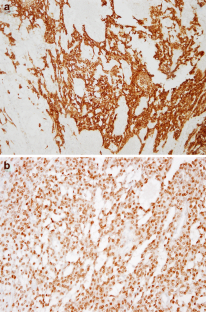

Microcystic stromal tumors (MCST), first described in 2009 by Irving et al., are rare ovarian neoplasms. The entity was introduced into the 2014 WHO classification of tumors of female reproductive organs in the group of sex cord-stromal tumors, which is rather heterogeneous. We studied three cases of ovarian tumor with the characteristic morphological features and immunohistochemical marker profiles of MCST. The three tumors showed micro, and macrocystic patterns with solid areas, and were composed of small round to spindle-shaped cells, without atypia. The tumors diffusely and strongly expressed CD10, FOXL2, and nuclear β-catenin, but without immmunoreactivity for hormone receptors, calretinin, or inhibin. Genome analyses showed no somatic mutation of exon 1 of the FOXL2 gene and of exons 24 and 25 of DICER1 gene, the latter not having been reported previously. The patients are well, without evidence of tumor progression 1 to 10 years after diagnosis.

Fig. 1